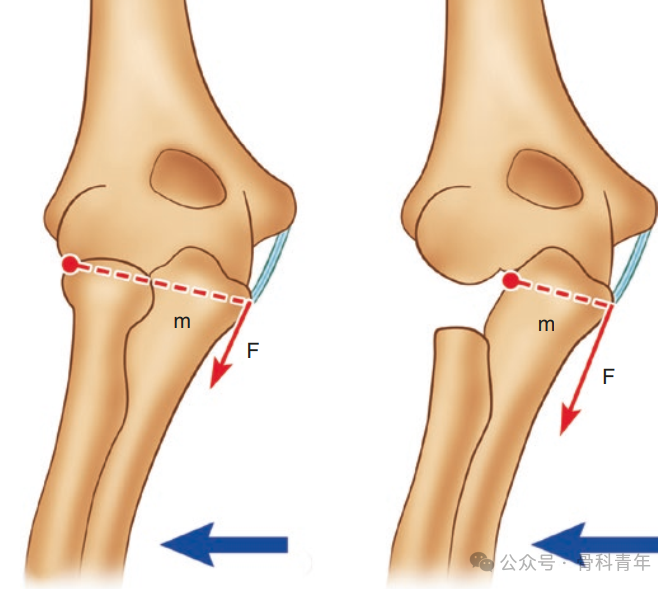

但桡骨头作为抵抗肘关节外翻的有效装置,以及在后外侧稳定中具有重要作用,因此非必要情况下不建议直接切除,首选内固定治疗。